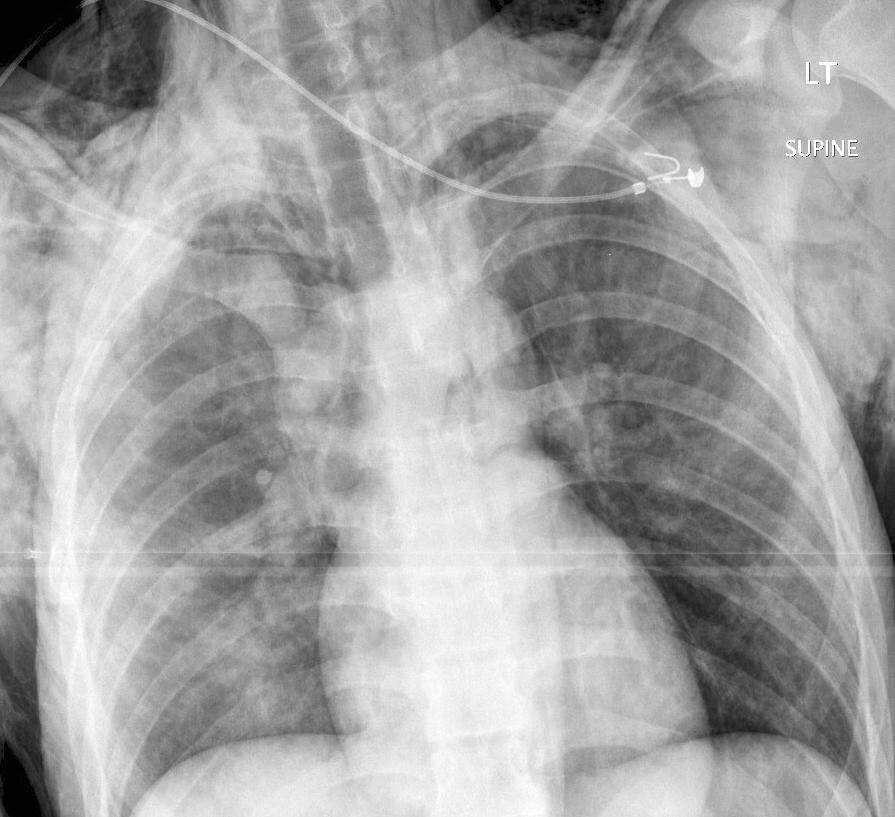

Gallery Blunt Chest Trauma Pneumothorax 9a bilat see CT

9a bilat see CT